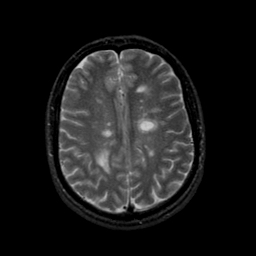

MR Study #9, April 14, 1991 -- Slice #34

[Home][Help][Clinical][Tour 1][Tour 2] Slice 34